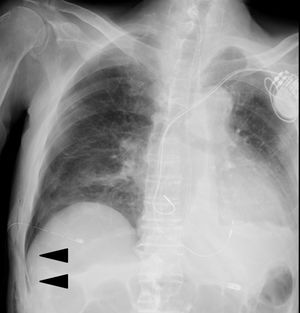

An 82-year-old man with an 81 pack-year smoking history underwent follow-up at our hospital for malignant lymphoma and chronic heart failure. He complained of dyspnea and was admitted to our hospital. He had emphysema, had previously undergone resection for cancer in the left lung, and was now diagnosed with right pneumothorax, exacerbation of heart failure, and CO2 narcosis. Artificial breathing management was performed, which continued for 3 days, and a chest tube was placed. Pneumothorax improved and air leakage disappeared; one day later, clamp test of the chest tube was done. However, a few days later, the deep sulcus sign was detected in his chest X-ray image (Fig. 1). Thus, we decided to continue chest drainage.

The deep sulcus sign on the chest X-ray image obtained in the supine position is an indicator of pneumothorax.1 In the reported patient, a narrow, sharp, and black air line forward to the abdominal region at the right costophrenic angle was observed, owing to the presence of air outside the lung and in the anterior and basal regions of the thoracic cavity in the supine position. Hyperaeration of the lungs may result in this sign falsely appearing in chest X-ray images of patients with chronic obstructive pulmonary disease. Nonetheless, identification of the deep sulcus sign on chest X-ray images obtained in the supine position can be useful for early diagnosis of pneumothorax.